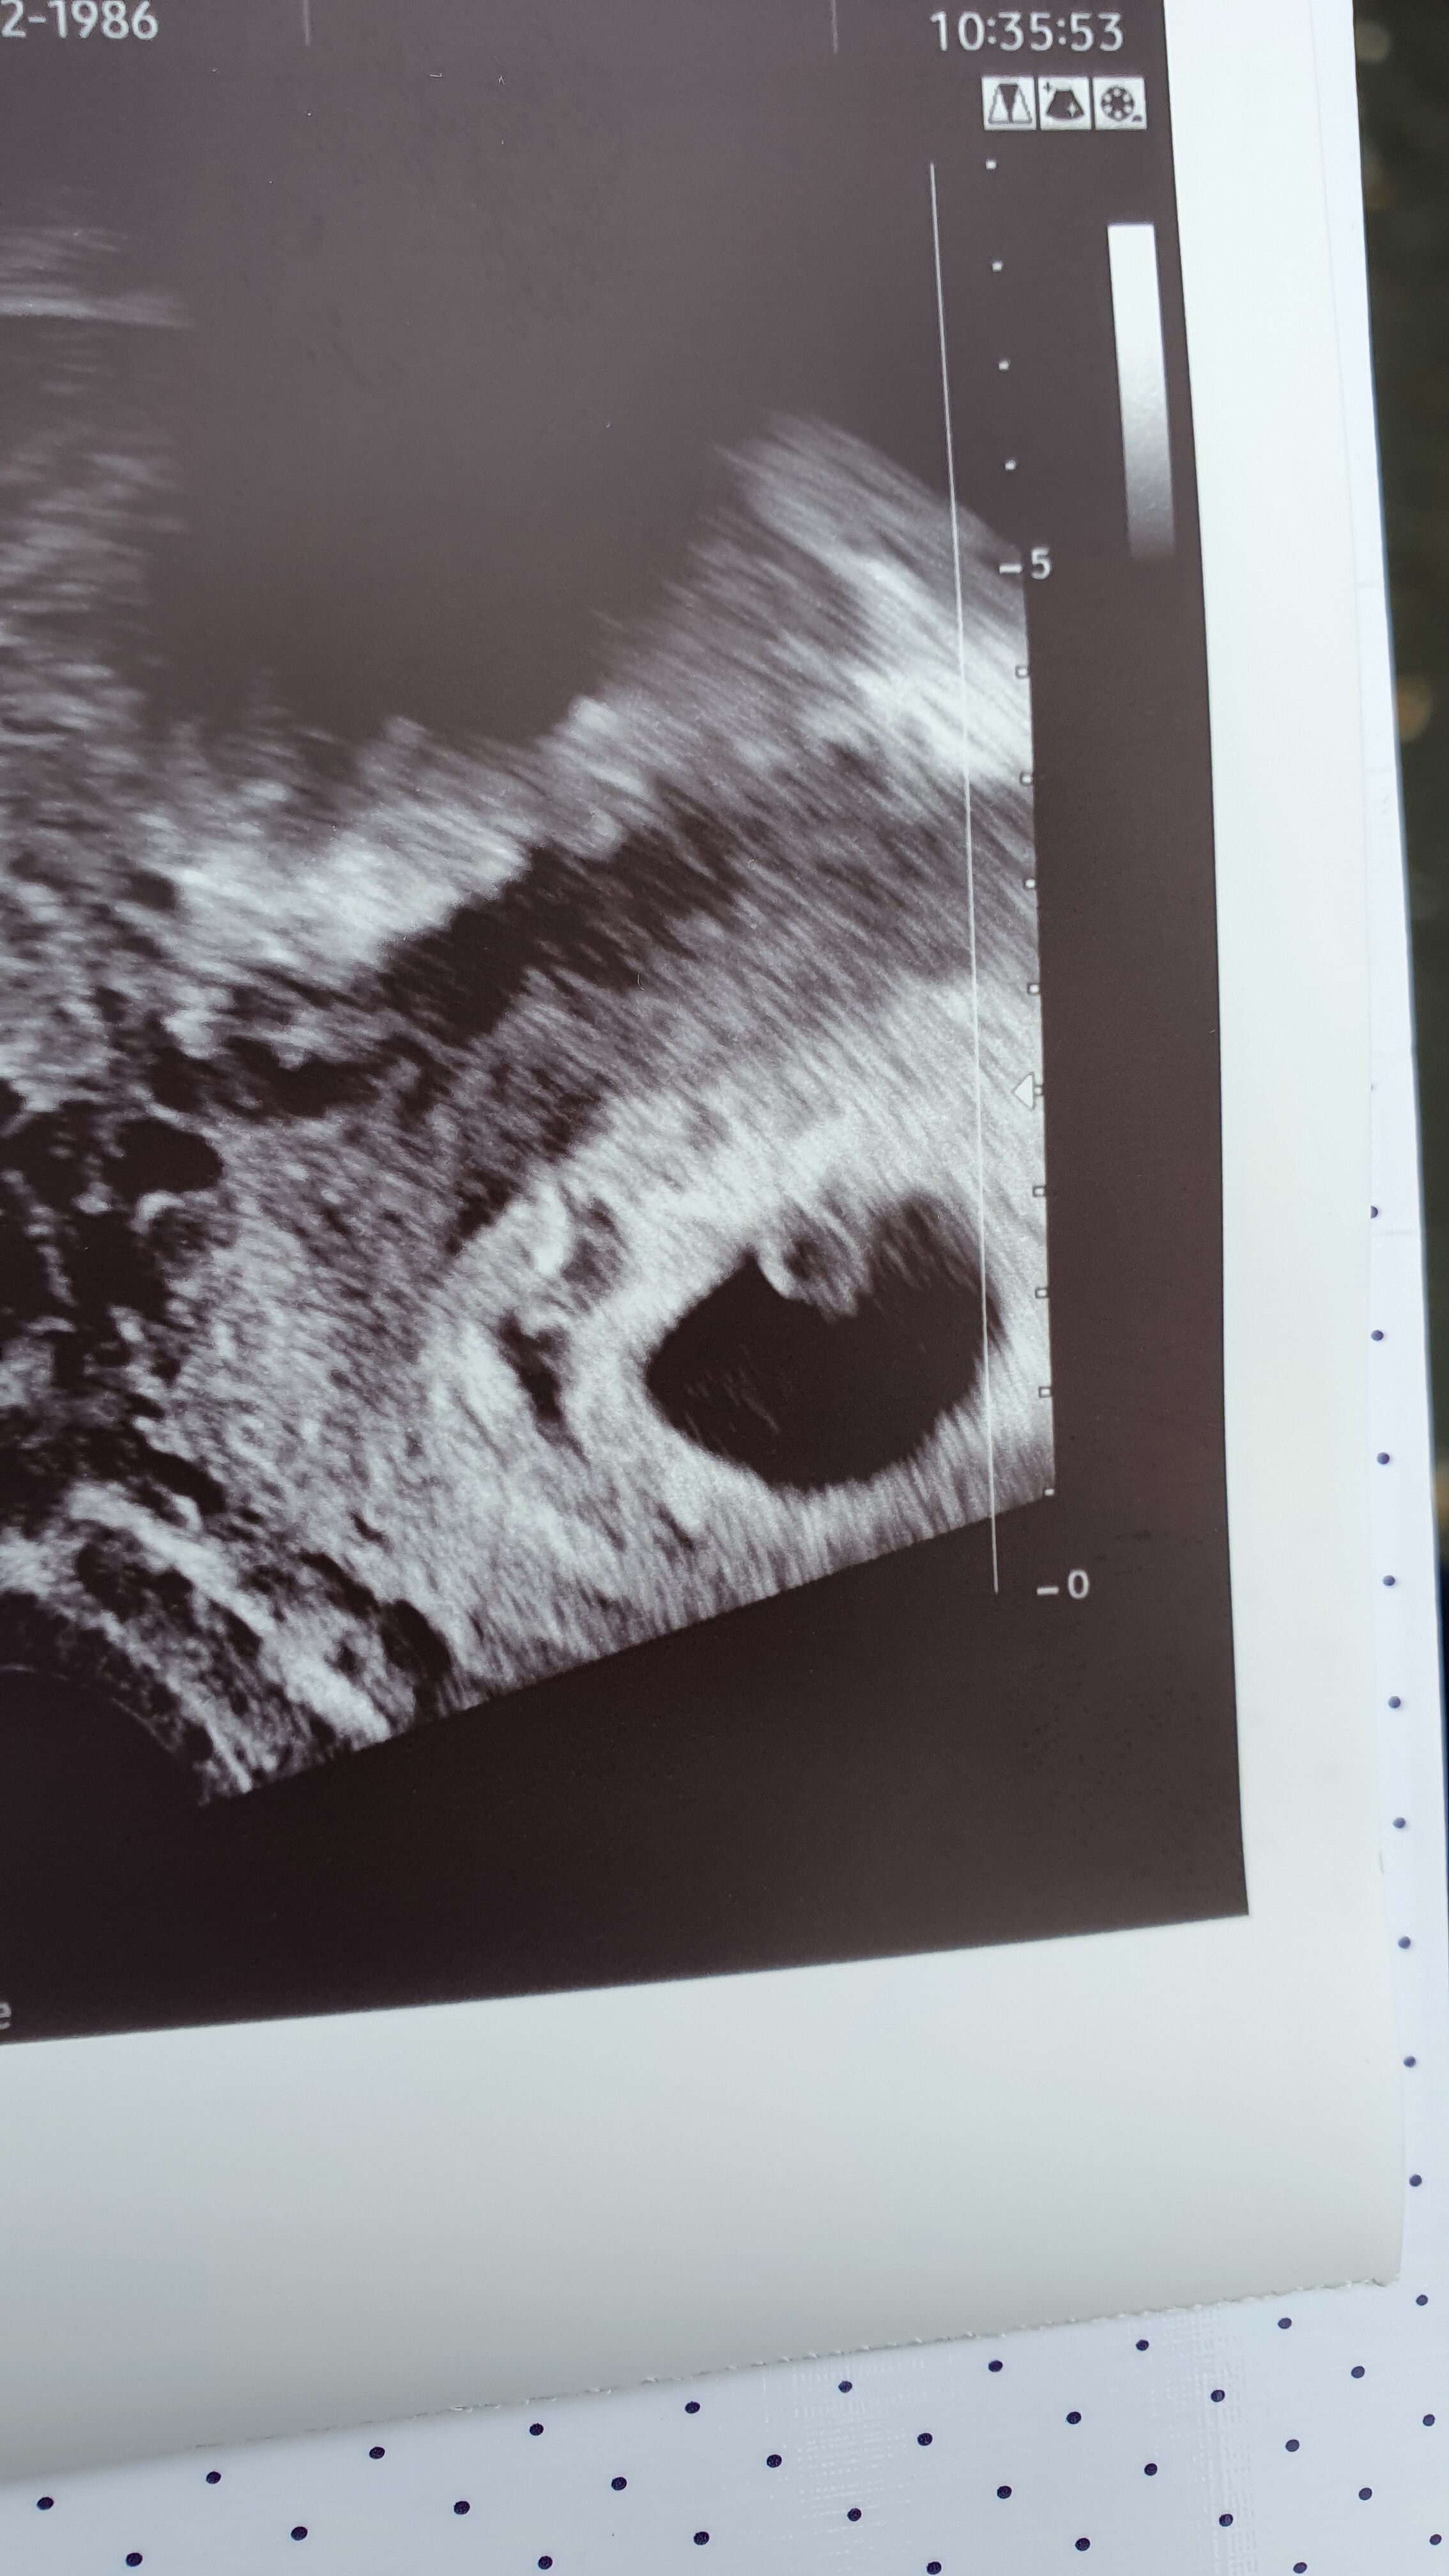

Jestem ,już po wizycie. Wszystko jest dobrze,

Bąbel ma 4,7mm, serduszko bije, słychać jest prawidło.

Kartę ciąży założy mi gin. Za 3 tygodnie.

Póki co termin pasuje idealnie z terminem z om czyli 18.06.

Pobrano mi krew, niestety badania genetyczne z krwii nadal u nas nie są refundowane, ale chętnie je wykonamy. Mam również zrobić termin na usg genetyczne w plradni.